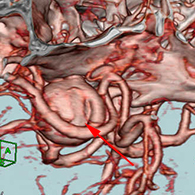

<実際の手術所見>

<手術中の脳血管撮影画像>

瘤(こぶ)は消失

患者様は術前からあった左視力低下以外に神経症状なし。元気に自宅退院された。